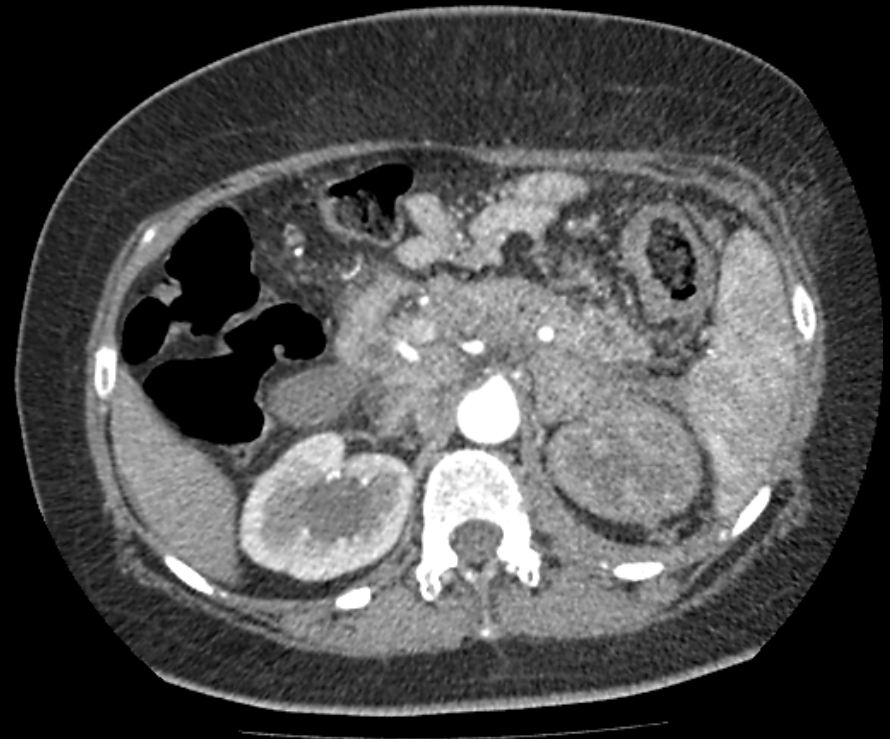

КТ органов брюшной полости. Печальная картина.

Пациентка 47 лет, состояние после оперативного лечения рака толстой кишки. Случай коллеги.

Состояние после срединной лапаротомии, колостома. КТ-признаки карциноматоза брюшной полости, распространенная забрюшинная и мезентериальная лимфаденопатия (мтс), инвазия левой боковой стенки мочевого пузыря с обструктивным опухолевым гидронефрозом, больше справа; псевдотуморозный панкреатит, парапанкреатит, вторичный  ишемический левосторонний колит, метастаз левого надпочечника. Мтс тел L4-S1. Вторичное снижение перфузии левой почки. Малый асцит. Холестаз.

Мне прислали только артериальную фазу из-за проблем с трафиком, но cказали, что почка работает. Гипоперфузия, вероятно, из-за сдавления левой почечной артерии со стороны парааортальных лимфоузлов. Нижняя мезентериальная артерия также сдавлена, вероятно в этом причина отёка подслизистого слоя левой половины ободочной кишки.

Селезенка в артериальную фазу часто имеет пятничтую структуру из-за трабекулярного строения. Поражение было в прямой кишке, удалена матка, резецирована часть прямой и сигмы.

Ну, с псевдотуморозным панкреатитом (увеличение, отек головки и тела железы с расширением вирсунга в хвосте) можно поспорить, хотя особой принципиальности нет, наверное. Холедох расширен.